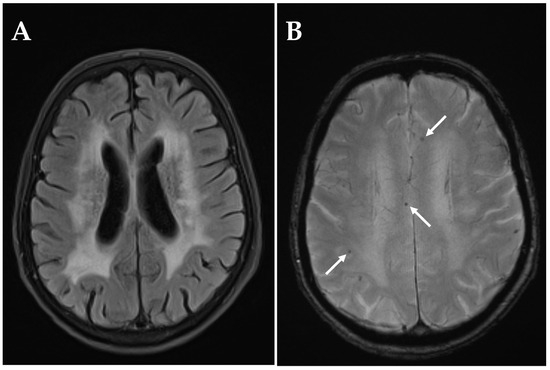

Acute Ischemic Stroke in Non-Arteritic Anterior Ischemic Optic Neuropathy

by Victor Wenzel, Leon Alexander Danyel, Sophia Meidinger, Eberhard Siebert, Theresia Knoche and Charlotte Pietrock

Diagnostics 2025, 15(24), 3192; https://doi.org/10.3390/diagnostics15243192 - 14 Dec 2025

Background: Non-arteritic anterior ischemic optic neuropathy (NAION) is a neuroophthalmological disorder characterized by impaired blood flow to the optic nerve head. There is uncertainty about whether, in some cases, NAION may be caused by proximal embolism of the posterior ciliary arteries. Diffusion-weighted magnetic [...] Read more.

Background: Non-arteritic anterior ischemic optic neuropathy (NAION) is a neuroophthalmological disorder characterized by impaired blood flow to the optic nerve head. There is uncertainty about whether, in some cases, NAION may be caused by proximal embolism of the posterior ciliary arteries. Diffusion-weighted magnetic resonance imaging (DWI-MRI) can provide evidence of concurrent cerebral infarction that may indicate a common embolic etiology. Methods: Adults with ophthalmological diagnosis of NAION who underwent cerebral DWI-MRI within 14 days from onset of visual impairment were included in a retrospective cohort study (2013–2021). DWI-MRI images were assessed for presence, location, and type of ischemic stroke by a board-certified neuroradiologist blinded for clinical patient data. Results: Among 122 patients (mean age 64.6 ± 11.9 years), DWI-MRI indicated acute/subacute ischemic stroke in three cases (2.5%), all located within the anterior circulation in the territory of the left middle cerebral artery and ipsilateral to the affected eye in two cases (1.6%). Ischemic stroke location was cortical in one case (0.8%) and subcortical in two cases (1.6%). Acute ischemic stroke indicated by a hyperintense DWI signal and corresponding low ADC was present in one patient (0.8%). Two patients (1.6%) had subacute ischemic stroke (hyperintense DWI signal and normal or elevated ADC signal). Only one NAION patient (0.8%) had acute embolic stroke corresponding to the vascular territory of the affected eye. Conclusions: Concurrent embolic ischemic stroke in NAION is exceedingly rare. Our findings support the prevailing pathophysiological theory of NAION as a non-embolic disease. Full article

Show Figures

Figure 1